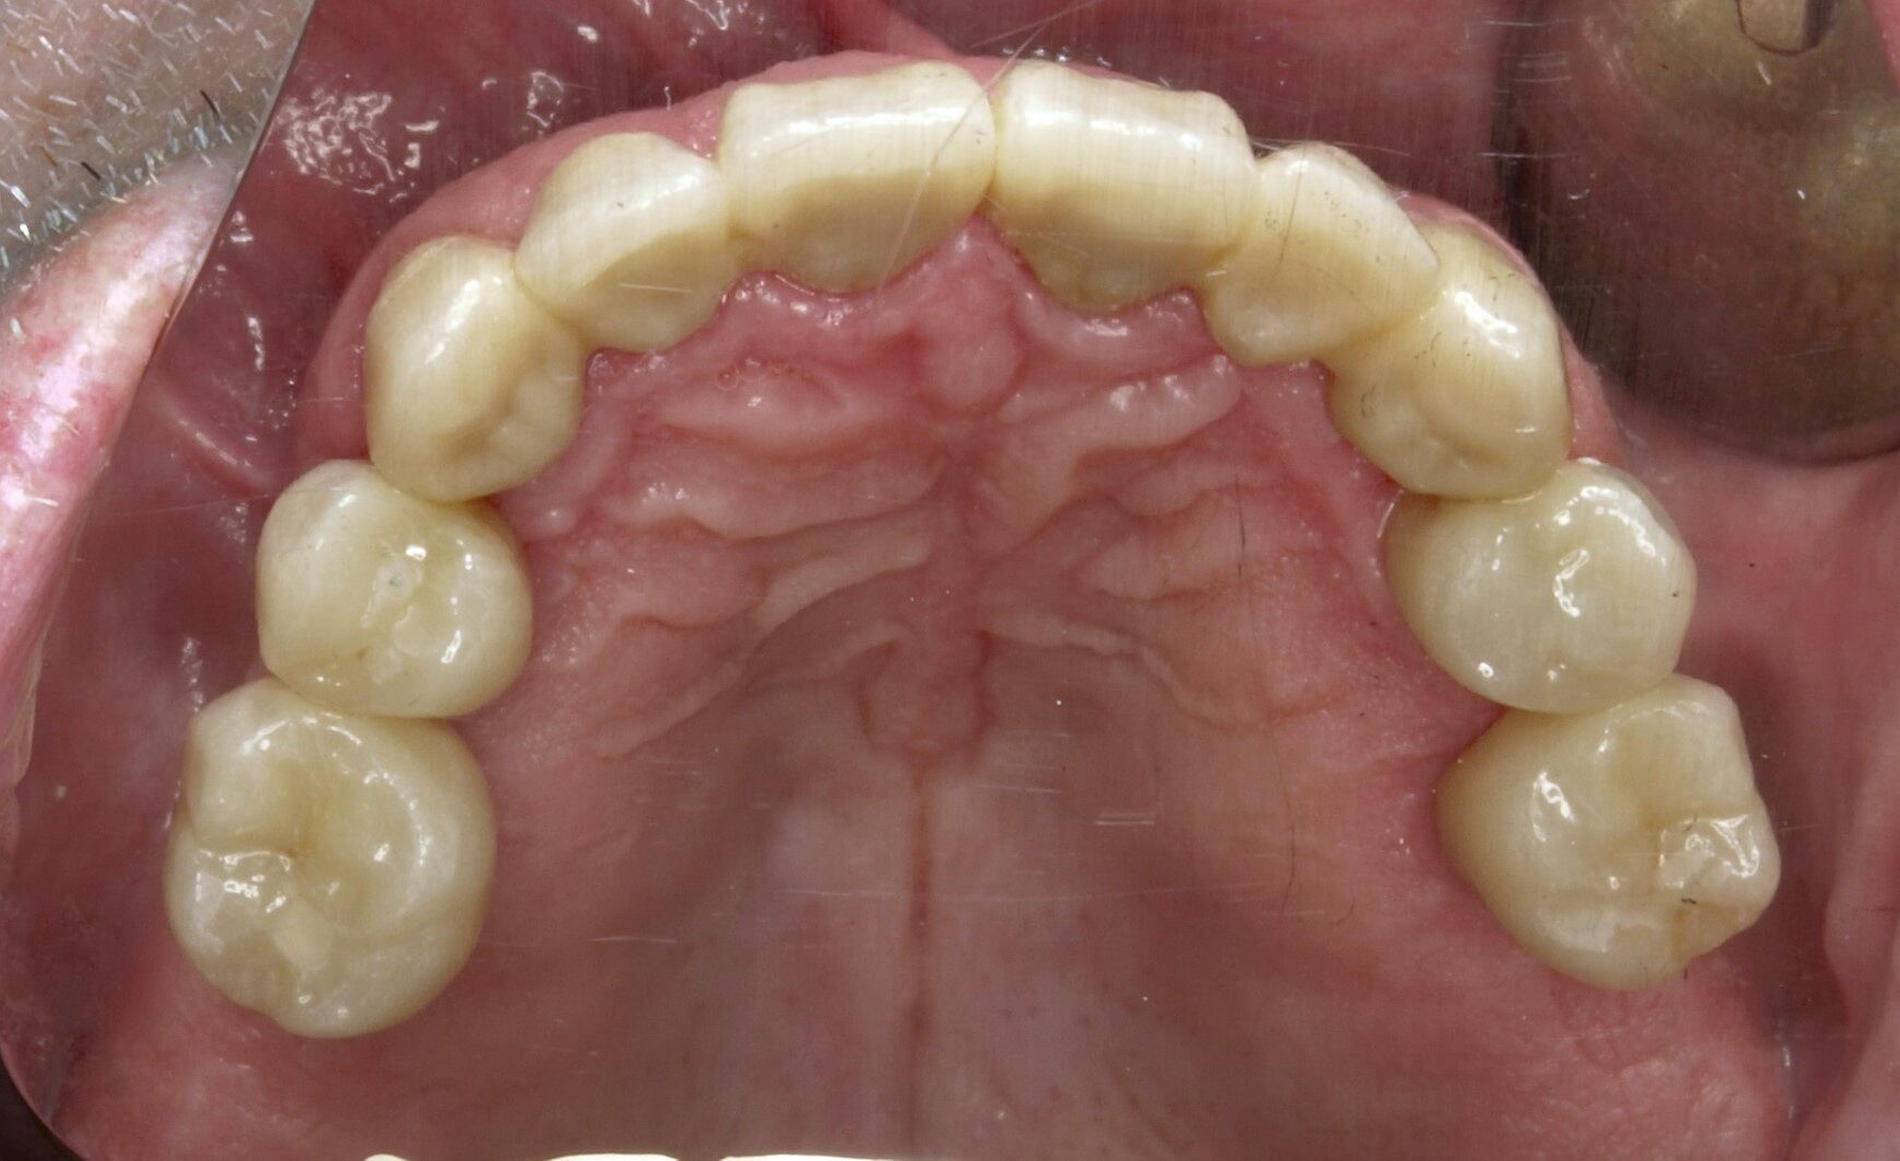

Nachdem die Einheilkäppchen entfernt und die Scanbodies in die Implantate eingeschraubt wurden, erfolgte der Intraoralscan (Abbildung 8c). Der festsitzende Zahnersatz wurde im zahntechnischen Labor designt und aus monolithischem Zirkonoxid gefräst. Die Kronen konnten schließlich selbstadhäsiv auf den Stümpfen befestigt werden. Das Einschrauben der Implantatkronen erfolgte mit Drehmomentschlüssel auf 35 Ncm nach Herstellerangabe. Die Schraubkanäle wurden anschließend verschlossen. Mit dem Endergebnis (Abbildung 8d) zeigte sich der Patient auch im Recallverlauf hochzufrieden.

Um den Sitz der Implantatkronen nach dem Einsetzen zu prüfen, wurden intraorale Tubusaufnahmen im Sinne eines Baseline-Röntgens angefertigt (Abbildung 9). In den Folgeterminen wurde dem Patienten noch eine Aufbissschiene für den Oberkiefer eingegliedert, um etwaigem nächtlichen Bruxismus vorzubeugen. Für die Nachsorge empfiehlt sich ein halbjährliches Kontrollintervall.